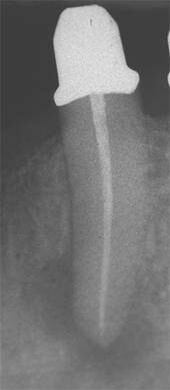

Schmerzhafter Zahn mit röntgenologisch eindeutiger Entzündung im Knochen (periapikale Aufhellung). -

Gleicher Zahn kurz nach erfolgter Wurzelkanalbehandlung. -